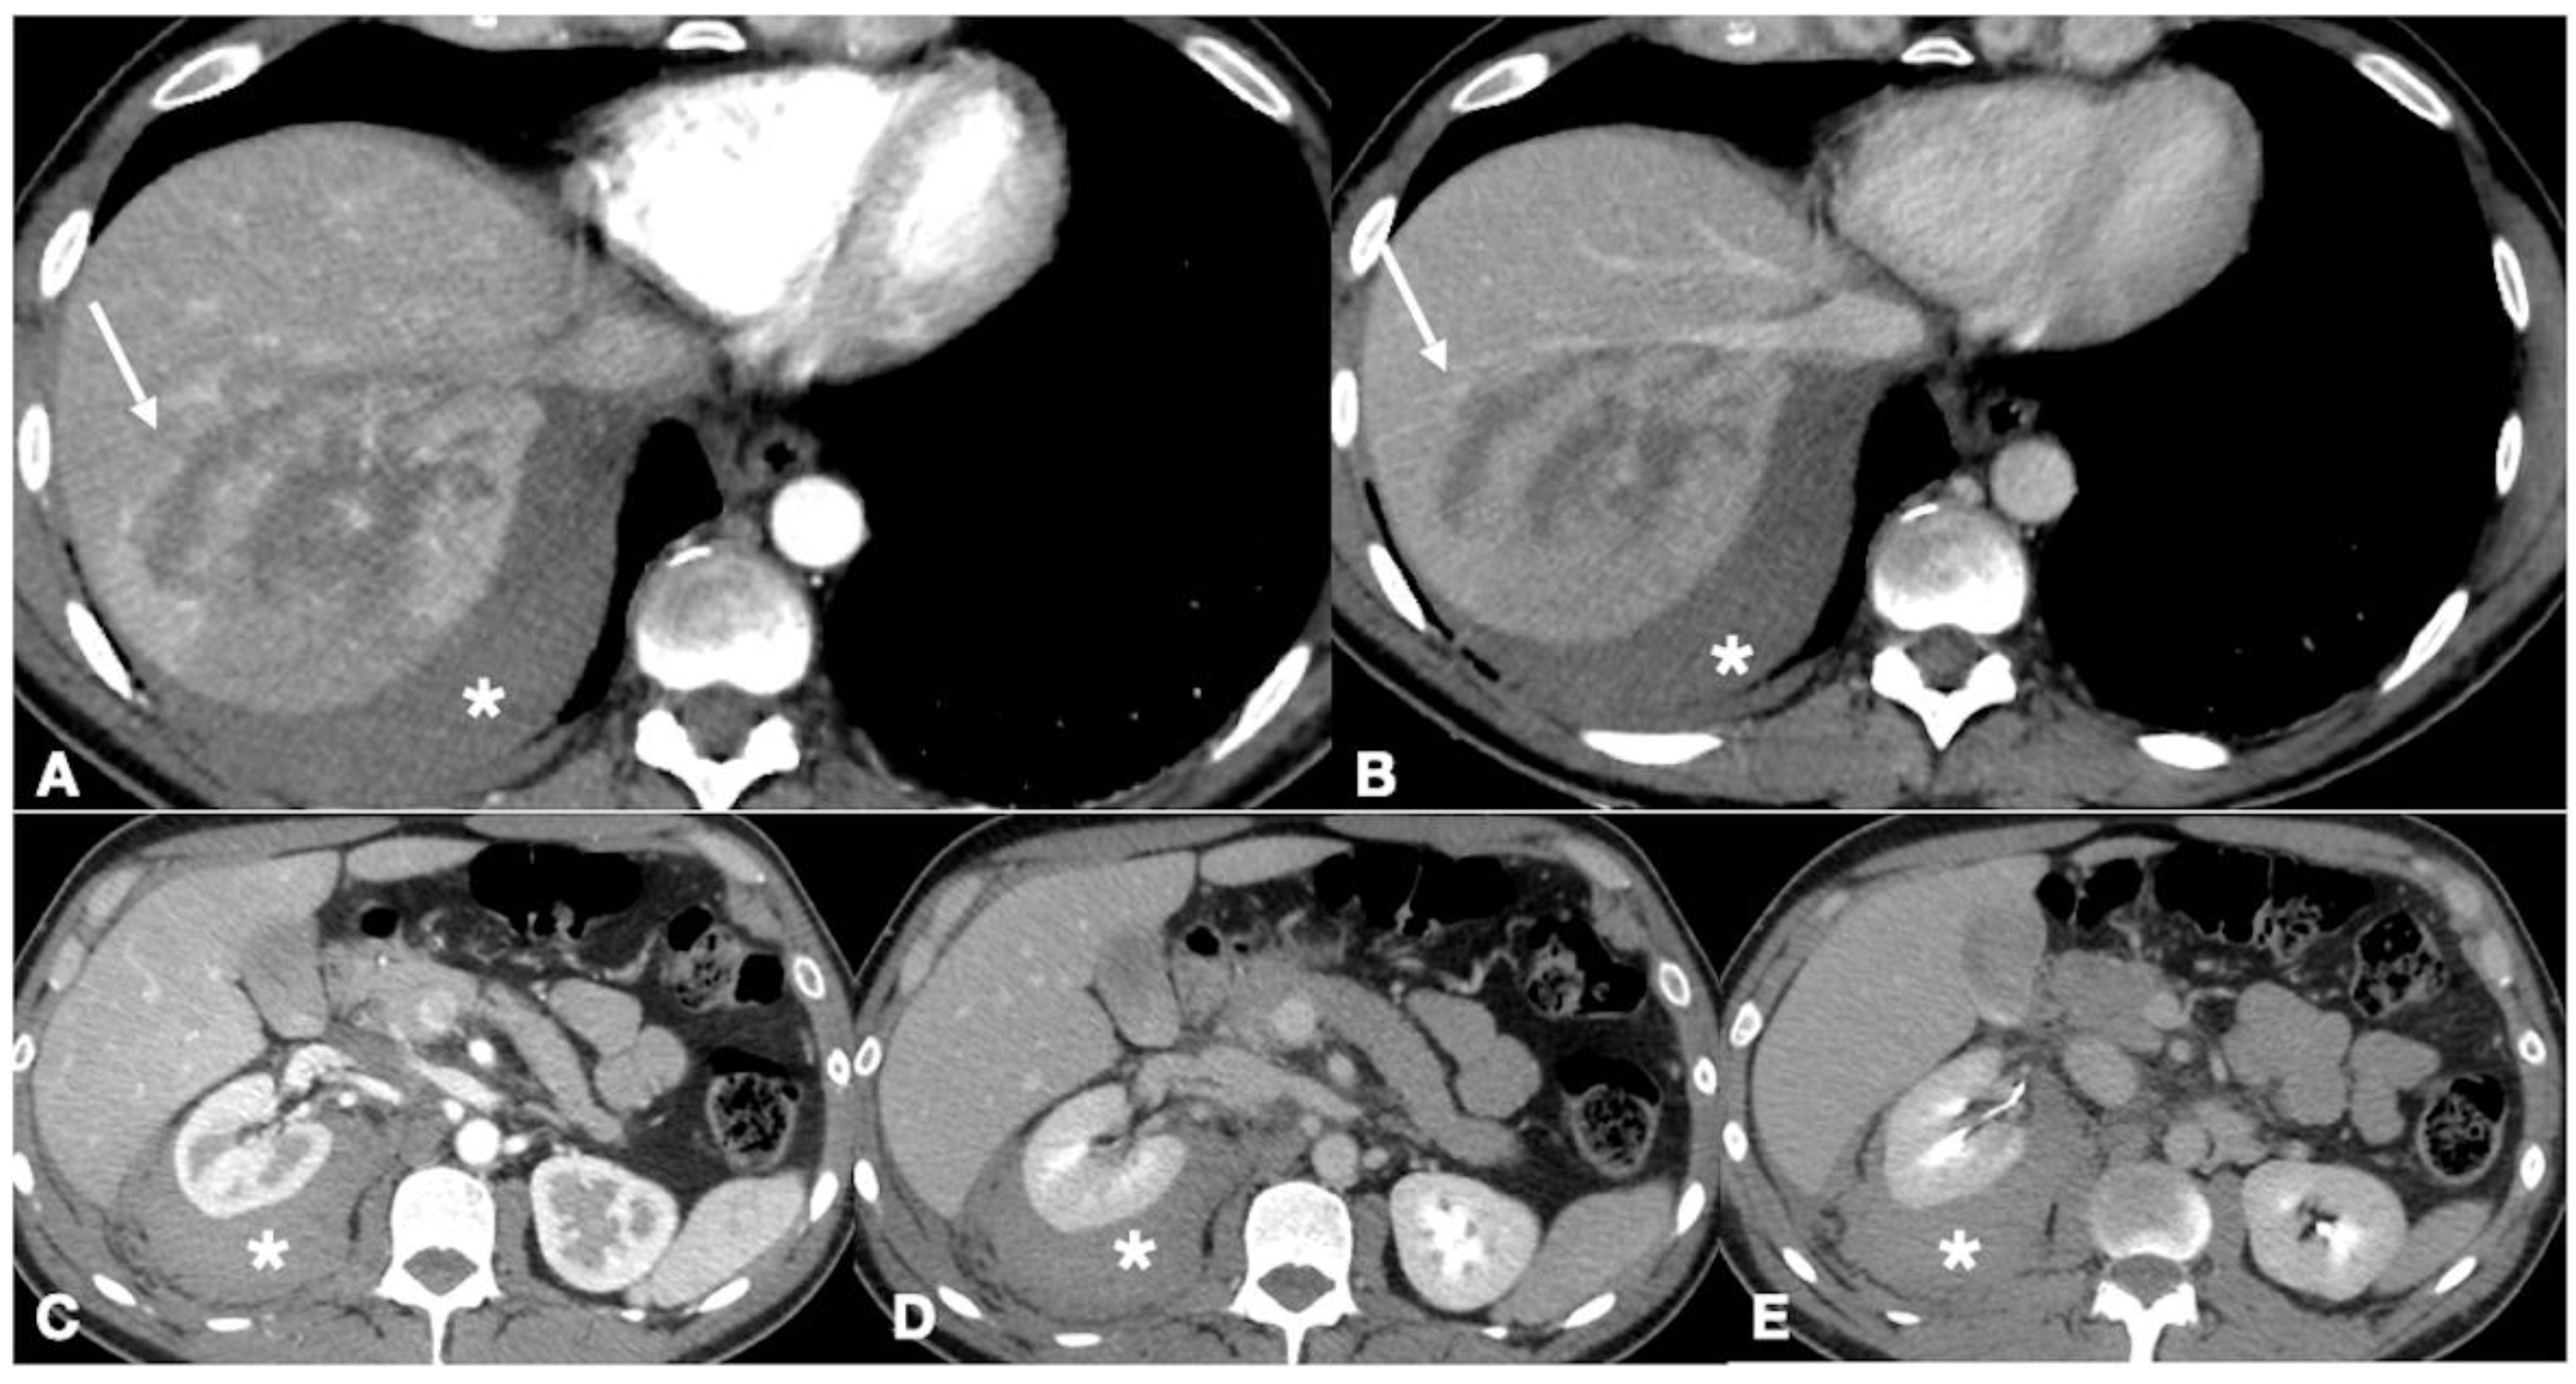

- Brillantino, A.; Iacobellis, F.; Festa, P.; Mottola, A.; Acampora, C.; Corvino, F.; Del Giudice, S.; Lanza, M.; Armellino, M.; Niola, R.; et al. Non-Operative Management of Blunt Liver Trauma: Safety, Efficacy and Complica-tions of a Standardized Treatment Protocol. Bull. Emerg. Trauma 2019, 7, 49–54. [Google Scholar] [CrossRef] [PubMed]

- Brillantino, A.; Iacobellis, F.; Robustelli, U.; Villamaina, E.; Maglione, F.; Colletti, O.; De Palma, M.; Paladino, F.; Noschese, G. Non operative management of blunt splenic trauma: A prospective evaluation of a standardized treatment protocol. Eur. J. Trauma Emerg. Surg. 2016, 42, 593–598. [Google Scholar] [CrossRef]

- Romano, L.; Giovine, S.; Guidi, G.; Tortora, G.; Cinque, T.; Romano, S. Hepatic trauma: CT findings and considerations based on our experience in emergency diagnostic imaging. Eur. J. Radiol. 2004, 50, 59–66. [Google Scholar] [CrossRef]

- Coccolini, F.; Panel, T.W.E.; Coimbra, R.; Ordonez, C.; Kluger, Y.; Vega, F.; Moore, E.E.; Biffl, W.; Peitzman, A.; Horer, T.; et al. Liver trauma: WSES 2020 guidelines. World J. Emerg. Surg. 2020, 15, 24. [Google Scholar] [CrossRef]